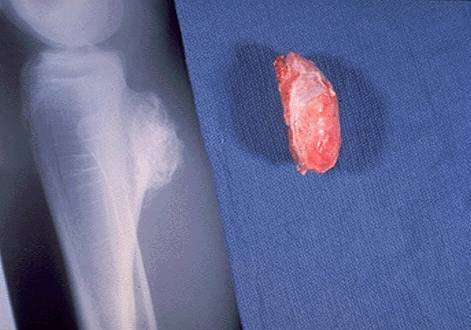

1)骨肉瘤

①骨肉瘤起发于原始间充质细胞的成骨细胞类,故名成骨肉瘤,恶性程度非常高。其特征为从肿瘤细胞直接形成骨和类骨

②多见于10—20岁,在成人也可因放射治疗,Paget氏病,甚至个别经久不愈的慢性骨髓炎引起骨肉瘤。

③临床症状:最早为疼痛,活动后疼痛加重,以夜间痛为重,患部包块并进行性增大,表面皮肤发热,静脉怒张

④X线表现:有溶骨性破坏和成骨性破Codman三角和日光放射征

⑤实验室检查:血沉、碱性磷酸酶、微量元素分析

⑥治疗:手术为主,辅助术前术后放疗化疗、免疫疗法

⑦骨肉瘤治疗的发展史

过去 手术切除5年生存率 5%—23%

现在 手术加辅助治疗5年生存率 60%---80%

骨肉瘤最常用的化疗药:

甲氨蝶呤、阿霉素、顺铂

slide0115_image079